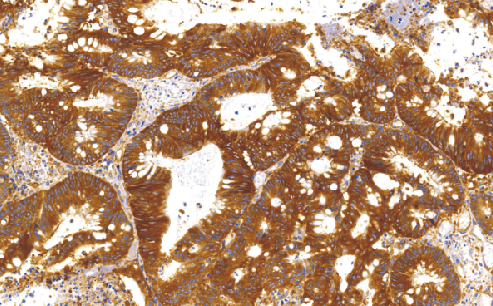

Lung-resistance related protein(LRP)鼠抗人肺耐药相关蛋白单克隆抗体

LRP是一种分子量为104-110kD的蛋白,亦属多药耐药(MDR)中的-种表型,可表达于许多肿瘤的组织中,阳性者预示对化疗不敏感,主要用于各种恶性肿瘤的研究。

- 阳性部位:胞质

- 适用组织:石蜡切片

- 预处理:热修复